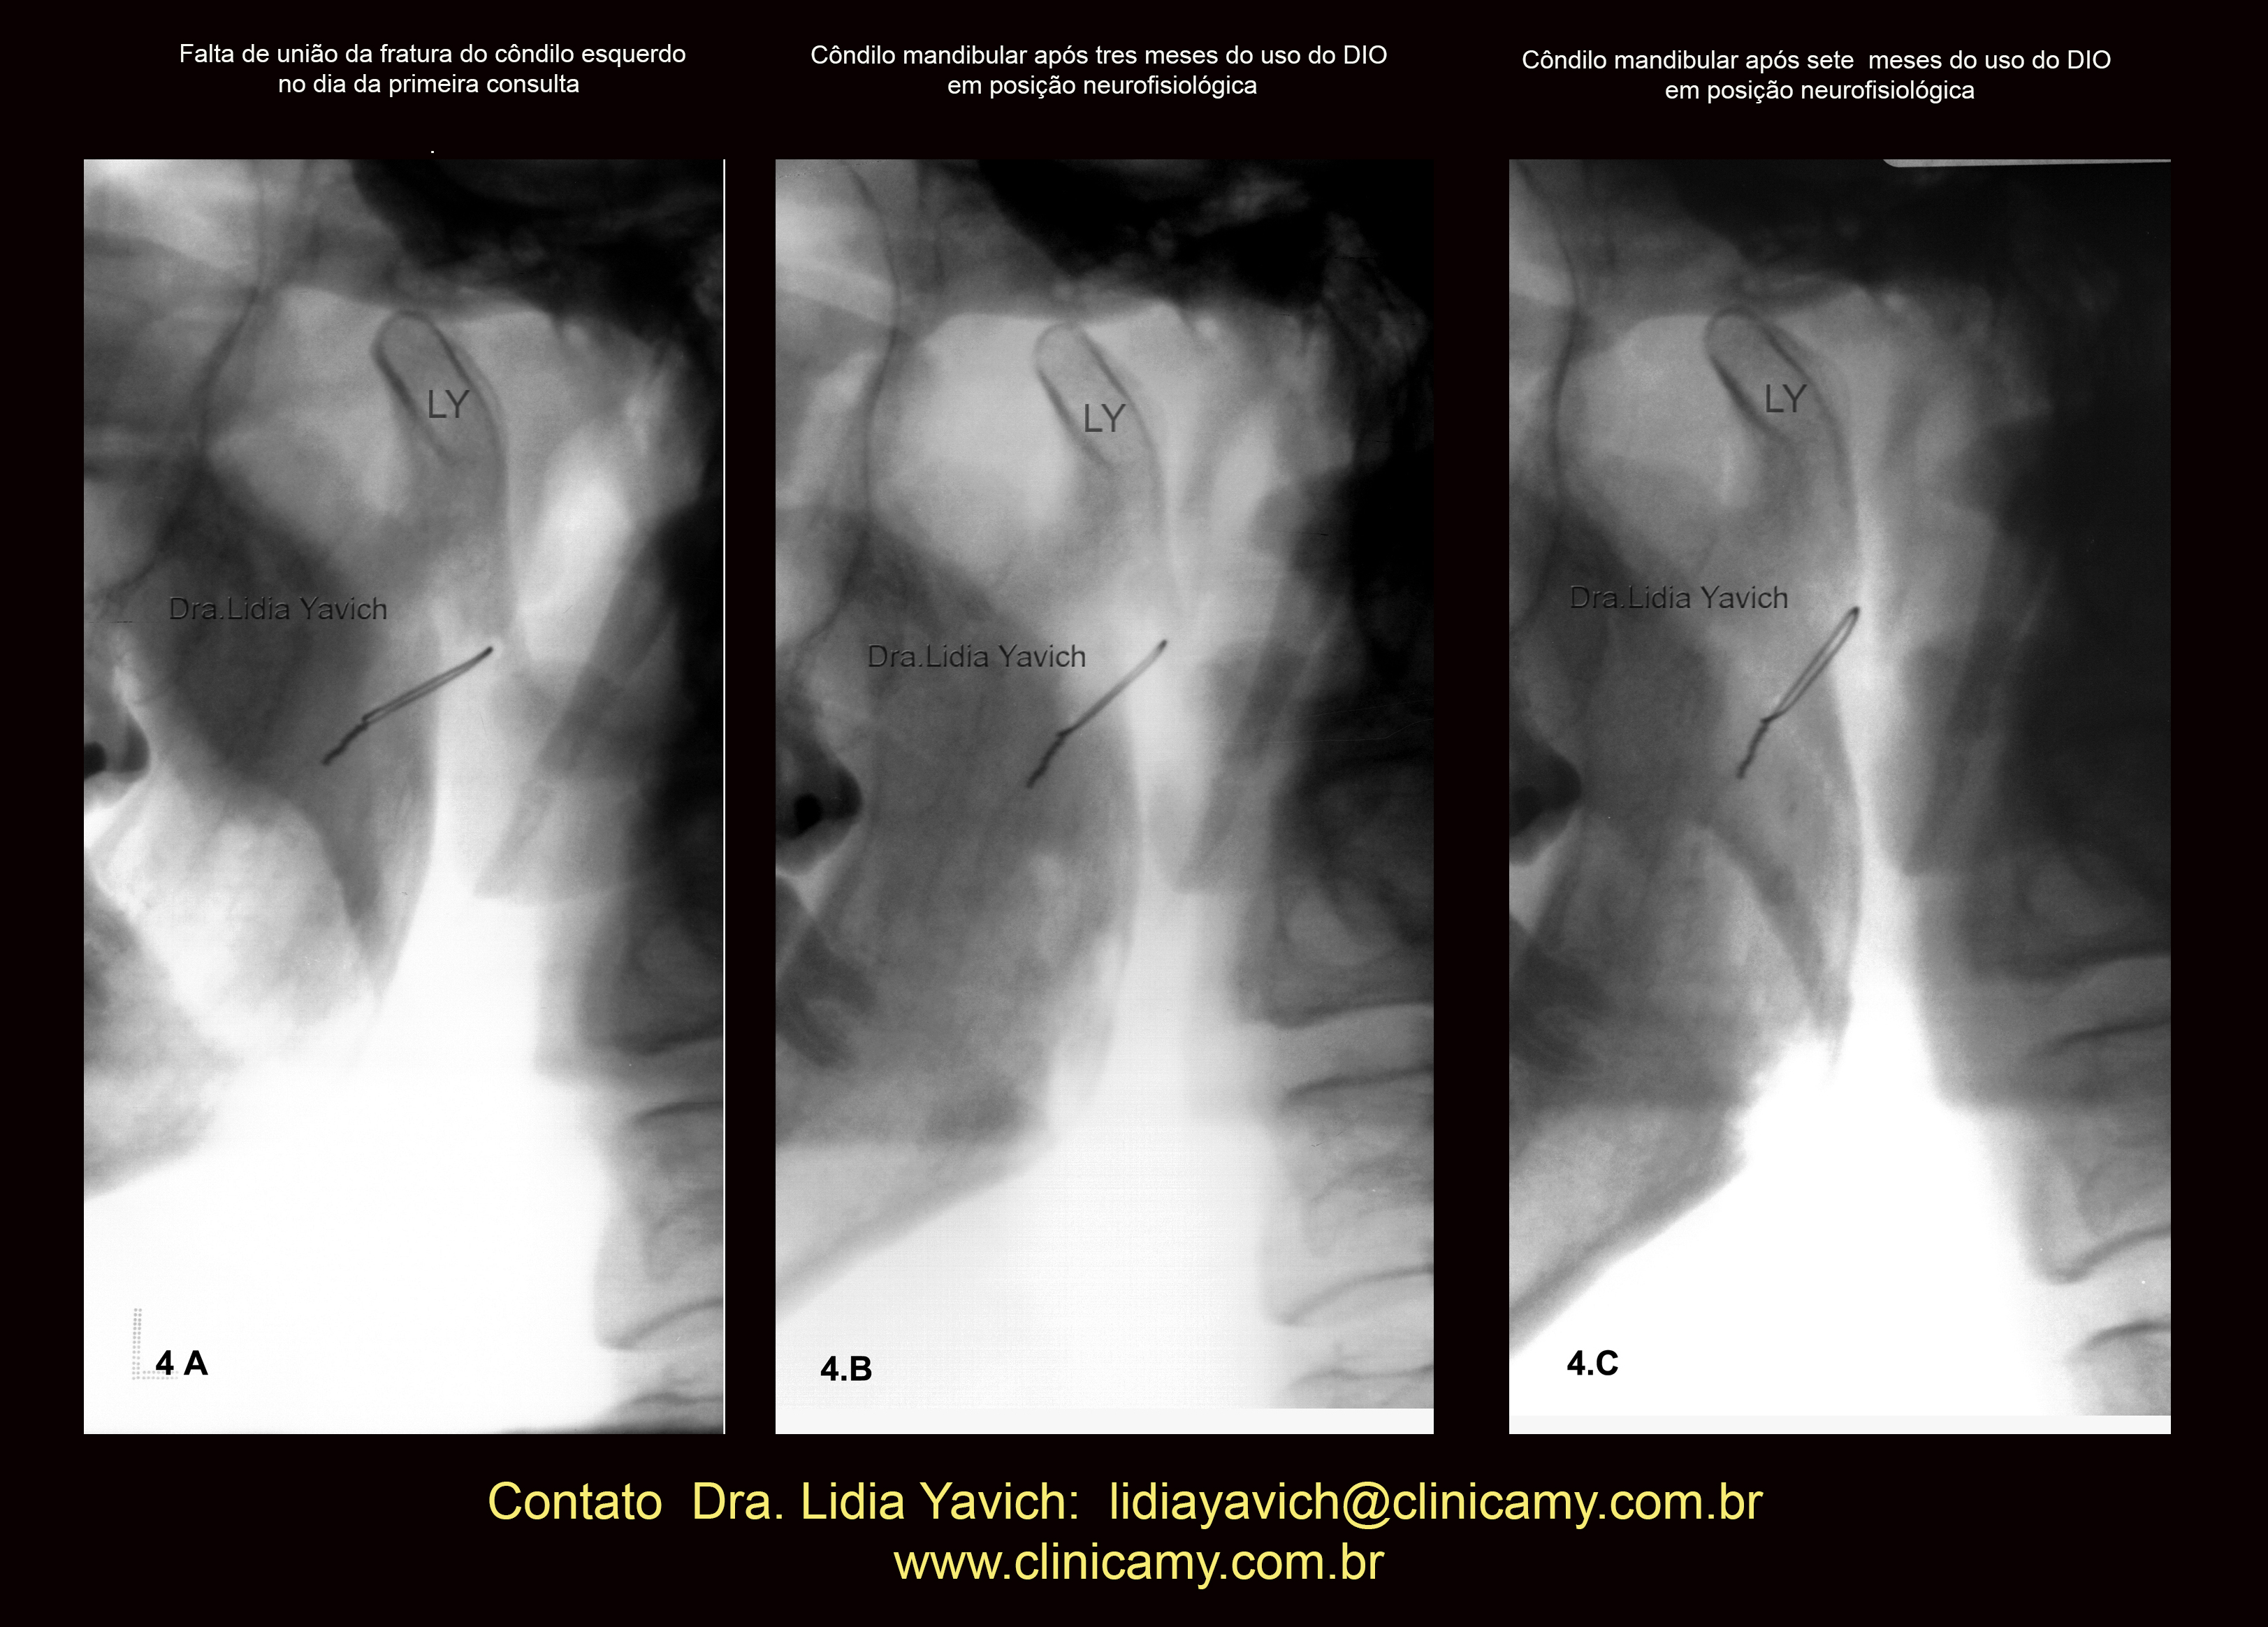

Imagem comparativa do côndilo mandibular esquerdo na primeira radiografia panorâmica do paciente no dia da consulta (4A).

Segunda radiografia panorâmica três meses após (4B)

Terceira radiografia panorâmica (4C) quatro meses após o segundo controle mostrando a melhora da posição do côndilo mandibular e a união do osso.

OBSERVAR A VERTICALIZAÇÃO DO FIO METÁLICO DA CIRURGIA

INVERSÃO DA COR da imagem comparativa do côndilo mandibular esquerdo na primeira radiografia panorâmica do paciente no dia da consulta (4A), segunda radiografia panorâmica três meses após (4B) e terceira radiografia panorâmica (4C) quatro meses após o segundo controle mostrando a melhora da posição do côndilo mandibular e a união do osso.

OBSERVAR A VERTICALIZAÇÃO DO FIO METÁLICO DA CIRURGIA.

Imagem comparativa do côndilo mandibular esquerdo na primeira radiografia panorâmica do paciente no dia da consulta (4A), segunda radiografia panorâmica três meses após (4B) e terceira radiografia panorâmica (4C) quatro meses após o segundo controle mostrando a melhora da posição do côndilo mandibular e a união do osso.

As imagens frontais da oclusão habitual no dia da consulta, quatro e sete meses após iniciado o tratamento estão também inseridas nesta imagem.